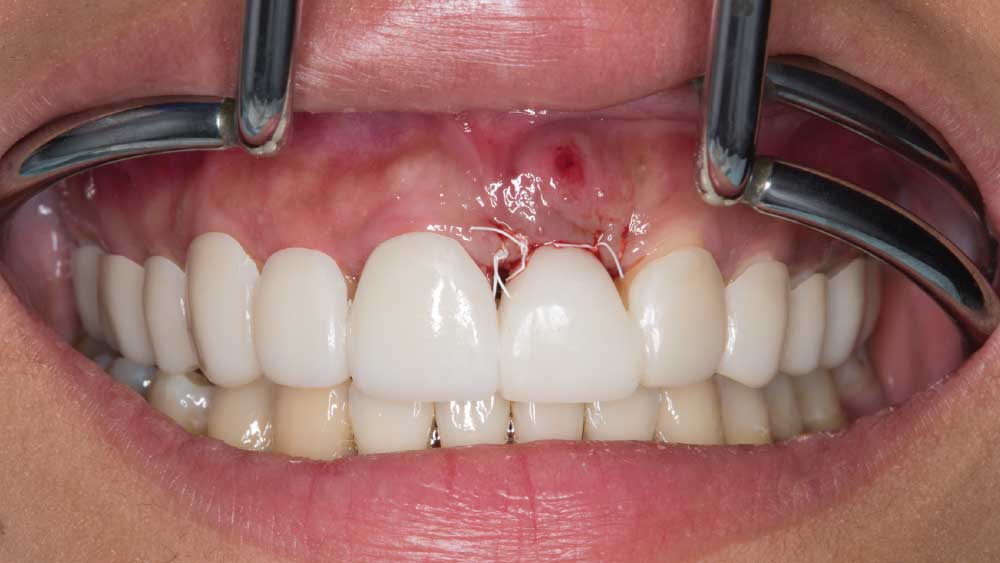

After conducting a thorough diagnostic examination, a vertical root fracture was noted, leaving the #9 central incisor malaligned and unstable. Due to the presence of significant vertical bone loss, extensive treatment for guided bone regeneration and a connective tissue graft would have been required prior to implant placement. After the patient was consulted on these factors, she opted against implant treatment. Once we discussed the remaining options, she decided on a bridge from #8–11 and a veneer on #7. Because she was congenitally missing tooth #10, placing a bridge to restore the edentulous area required preparing the adjacent canine and reshaping it to look like the missing lateral. I selected BruxZir® Esthetic Solid Zirconia as the best material to restore her beautiful smile. Not only does BruxZir Esthetic have superior strength compared to similar all-ceramic materials such as IPS e.max®, but it also has a translucent, natural-looking appearance. Sometimes clinicians think it is risky to do an all-ceramic bridge, but with a strong material like BruxZir Esthetic that has an average flexural strength of 870 MPa, doctors can confidently seat an anterior bridge that will produce long-lasting results. BruxZir has become such a popular material for dentists that it has been utilized to successfully fabricate more than 1.2 million bridges.

It was a four-month restoration process but a worthwhile journey. The outcome radically transformed Maria’s life. She no longer struggles to eat certain foods, nor does she lack confidence in her appearance. Instead, she feels great about herself and is able to talk confidently in front of people. Her BruxZir Esthetic veneer and bridge have given her a new lease on life. Now she is no longer afraid to share her smile with the world.